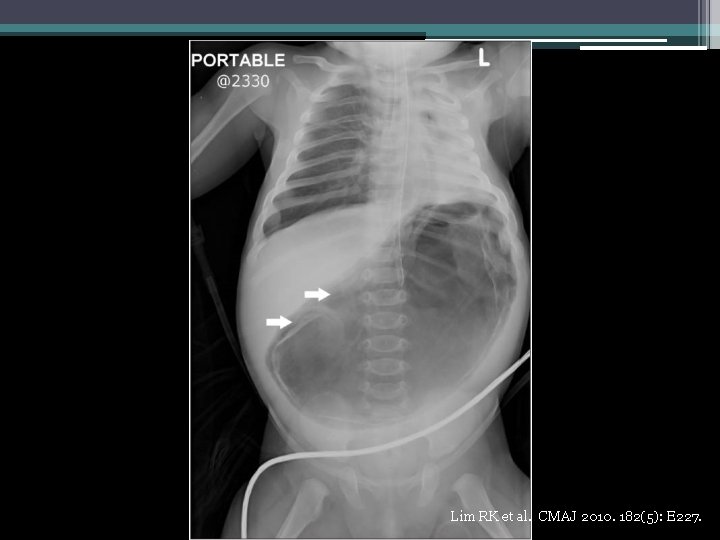

Lim RK et al. CMAJ 2010. 182(5): E 227.

Gastric emphysema in relation to gastric outlet obstruction • Well-reported in the pediatric literature • Most commonly due to pyloric stenosis ▫ Also duodenal stenosis, tumor, protracted vomiting • Mortality rate for gastric pneumatosis 41% in adults, 6% in children D’Cruz R et al. J Pediatr Surg 2008 ; 43: 2121 -3. Taylor D et al. Int Pediatr 2000; 15: 117 -20.